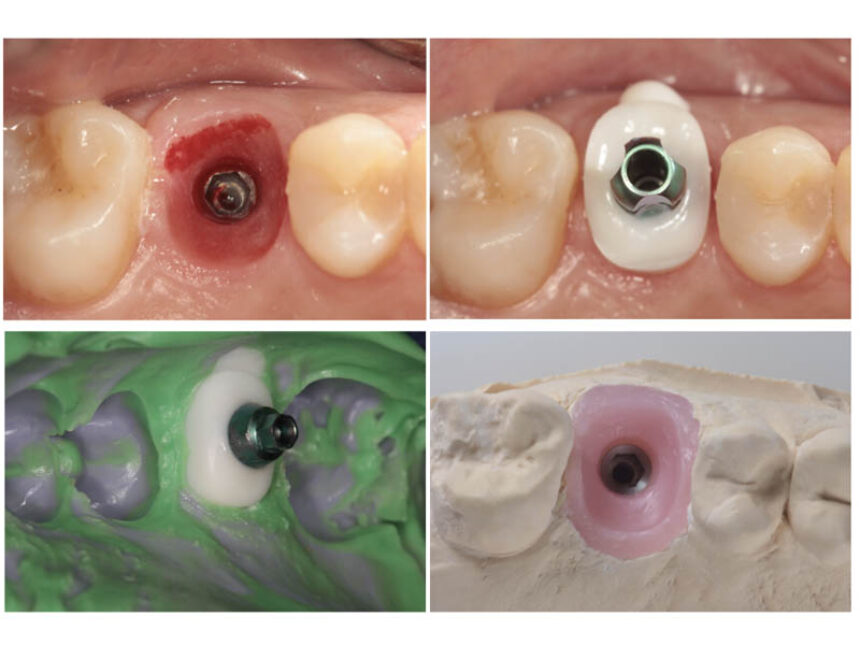

Hands-on Practice :

"A to Z.

Scan, Plan and execute fully guided anterior immediate implant and provisionalization with the use of Cervico”

Ioannis Vergoulis

Dimitris Chatziemmanouil